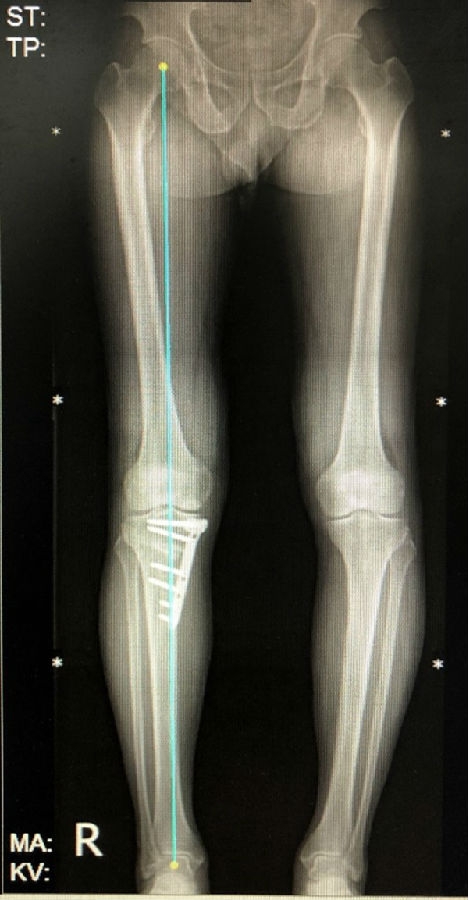

病例1:男,64岁,主诉左膝关节内侧疼痛6年余。MR提示骨坏死区占比为33.28%,矢状位病变区域前后径为26.42mm,半月板相对突出百分比(RPE)31.78%,同时存在胫骨侧来源的下肢内翻畸形(MPTA83°),关节线会聚角2°。

行关节镜检查+软骨摘除+微骨折+HTO术,术后随访2年恢复良好,活动自如,行走时无左膝关节疼痛不适。